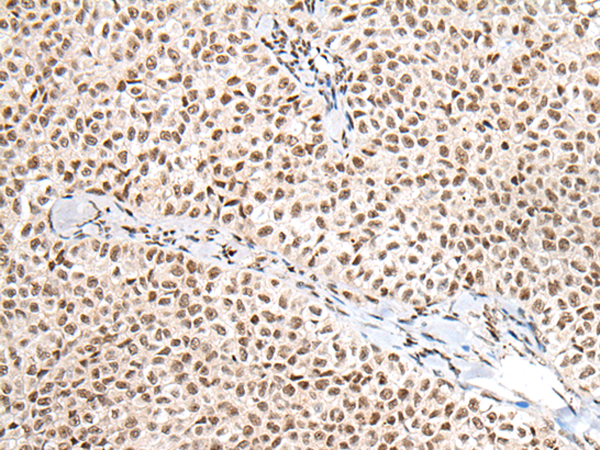

IHC positive control: |

Human ovarian cancer and human thyroid cancer |

IHC Recommend dilution: |

25-100 |